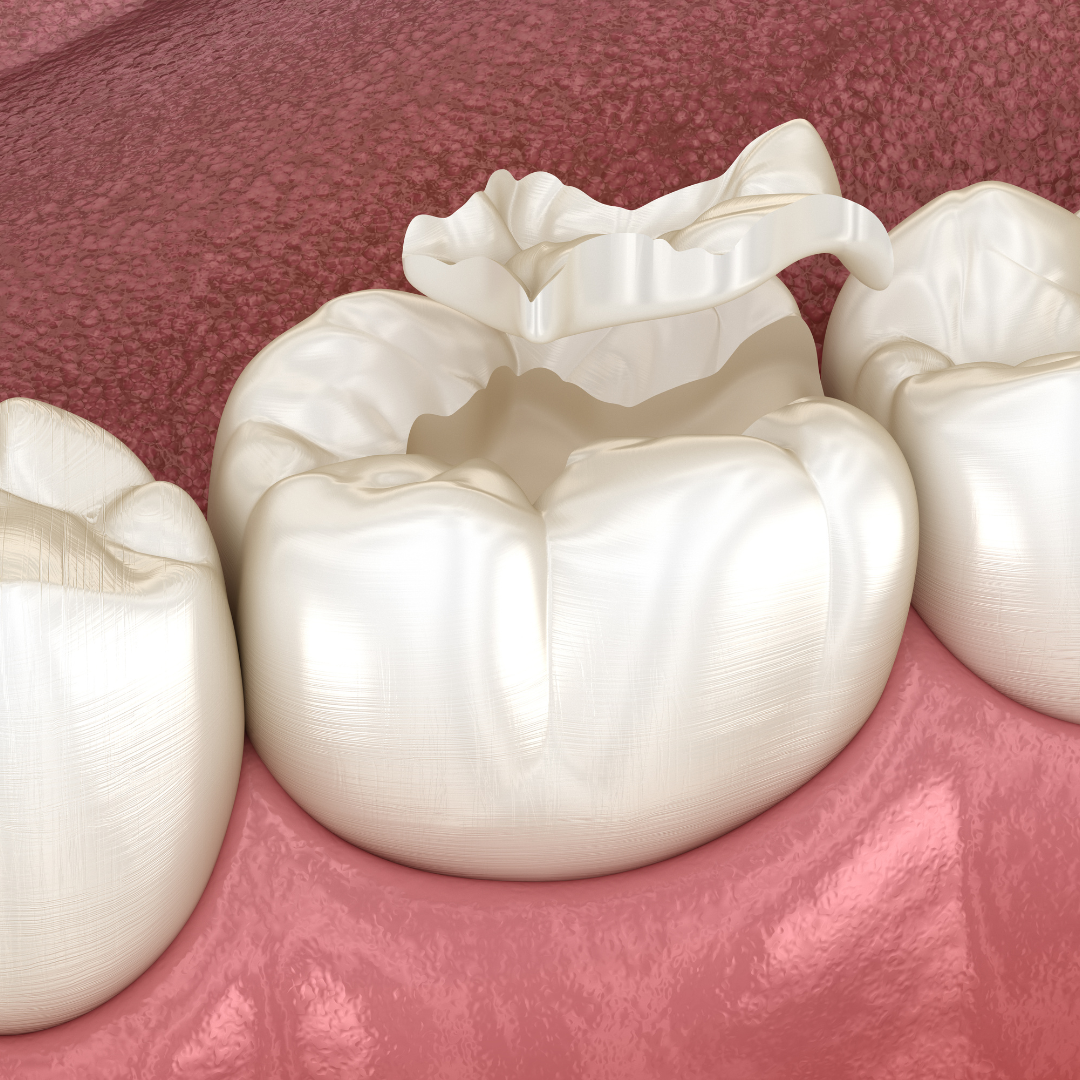

Inlays and Onlays

Also known as indirect fillings, these treatments

1. লাইট কিউর ফিলিং: আধুনিক পদ্ধতিতে দাঁতের গর্ত ভরাট করা।

2. কম্পোজিট ফিলিং: প্রাকৃতিক রঙের ফিলিং ব্যবহার করে দাঁতের সৌন্দর্য বজায় রাখা।